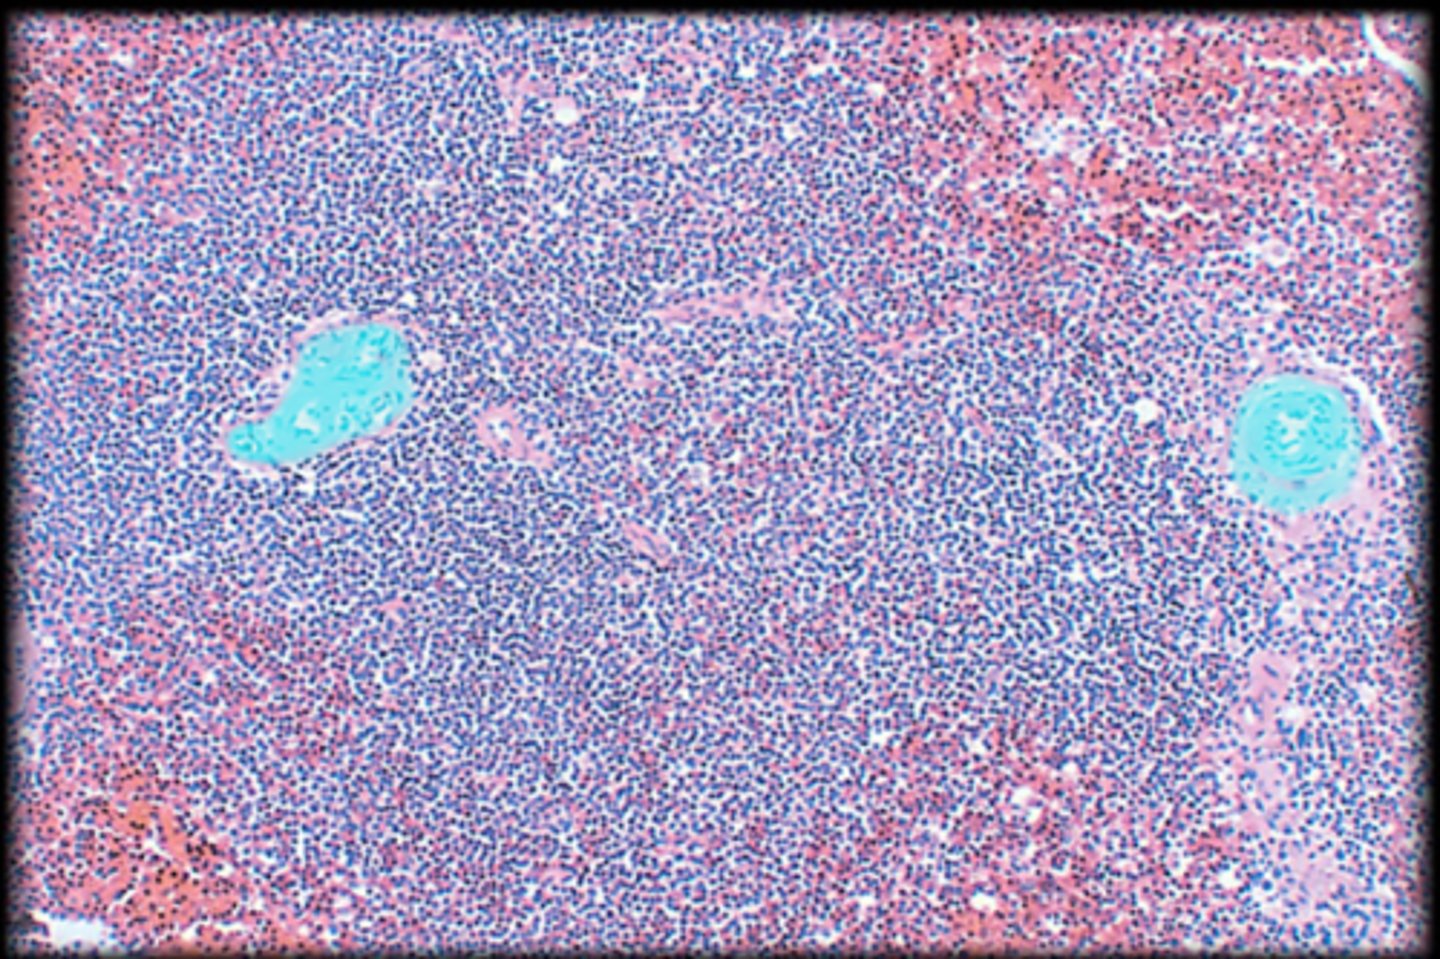

Spleen

central white pulp

red pulp

white pulp